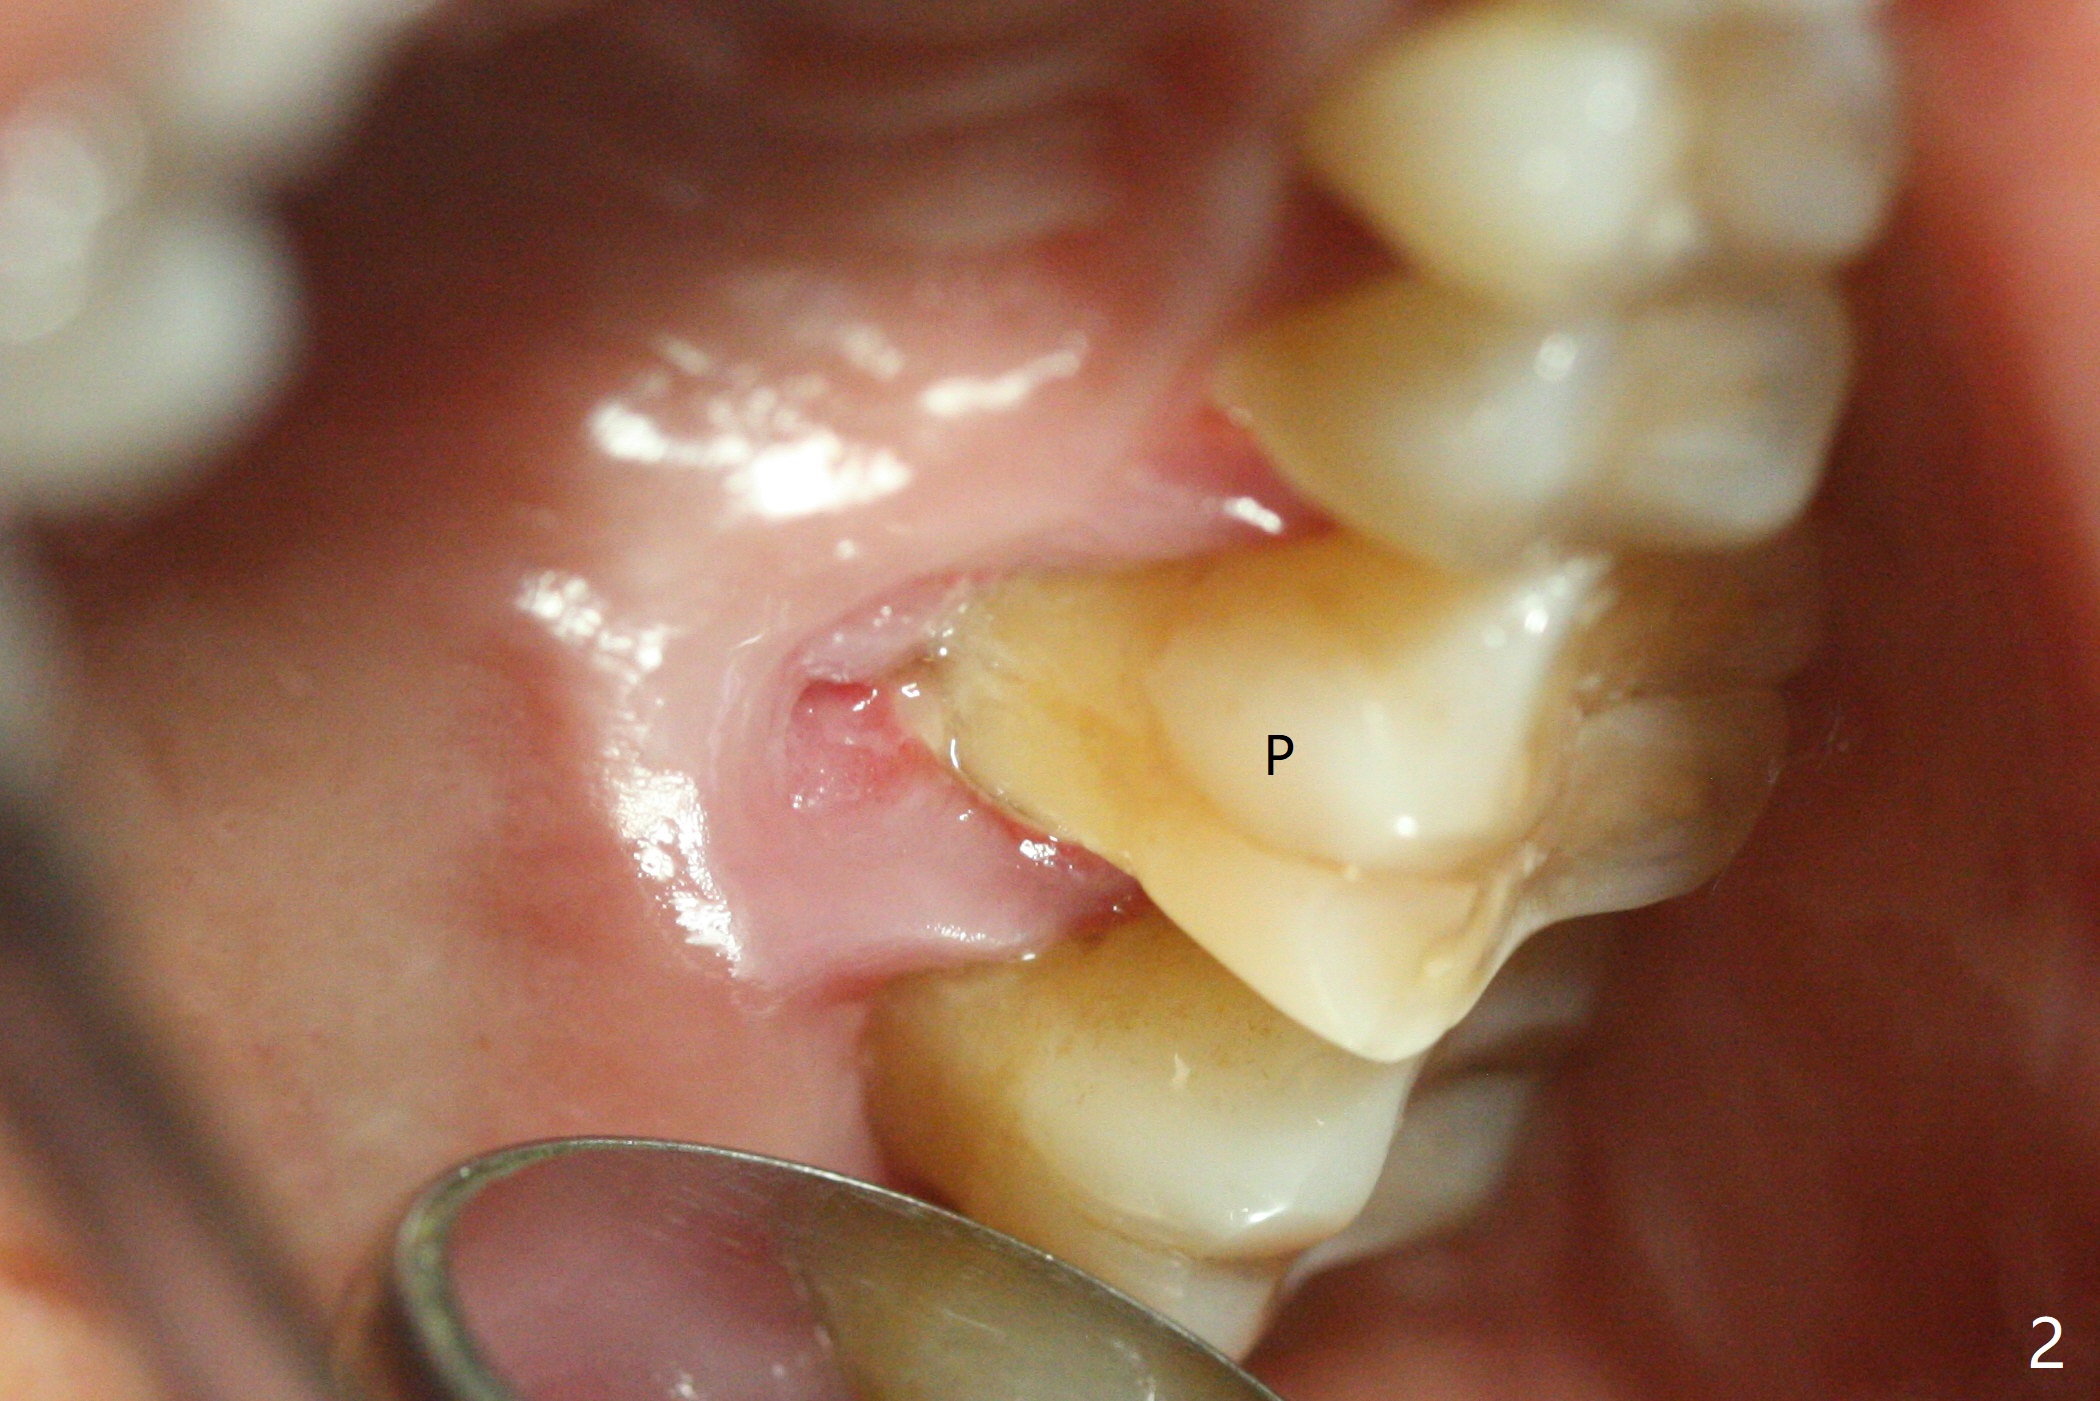

A 51-year-old woman with chronic periodontitis has difficulty masticating on the left side. The tooth #14 (Fig.1) has severe palatal gingival recession (Fig.2), apparently without palatal plate. CT will be taken prior to treatment. After extraction, PRF plug will be inserted to the palatal socket, while bone graft will be placed in the buccal ones. Two PRF membranes will be used for socket opening coverage. CT will be taken postop. The case will test whether PRF will regenerate bone by taking 4 months postop.

血小板纤维素膜(PRF)制作方法各式各样,今晚探讨的是L-PRF(L: 白细胞),作者认为L-PRF能促进骨再生,一般观点PRF只利于软组织愈合。51岁女,左上第一磨牙严重牙周炎(图一: 14),腭侧根暴露 (图二),拔除后,腭侧牙槽窝放置PRF,而颊侧牙槽窝放置骨粉,估计骨粉放在腭侧窝,可能不容易固定。万一自我发明PRF不能促进骨形成,植体能植入颊侧牙槽窝。术前术后(即刻,四个月)拍摄局部CT。